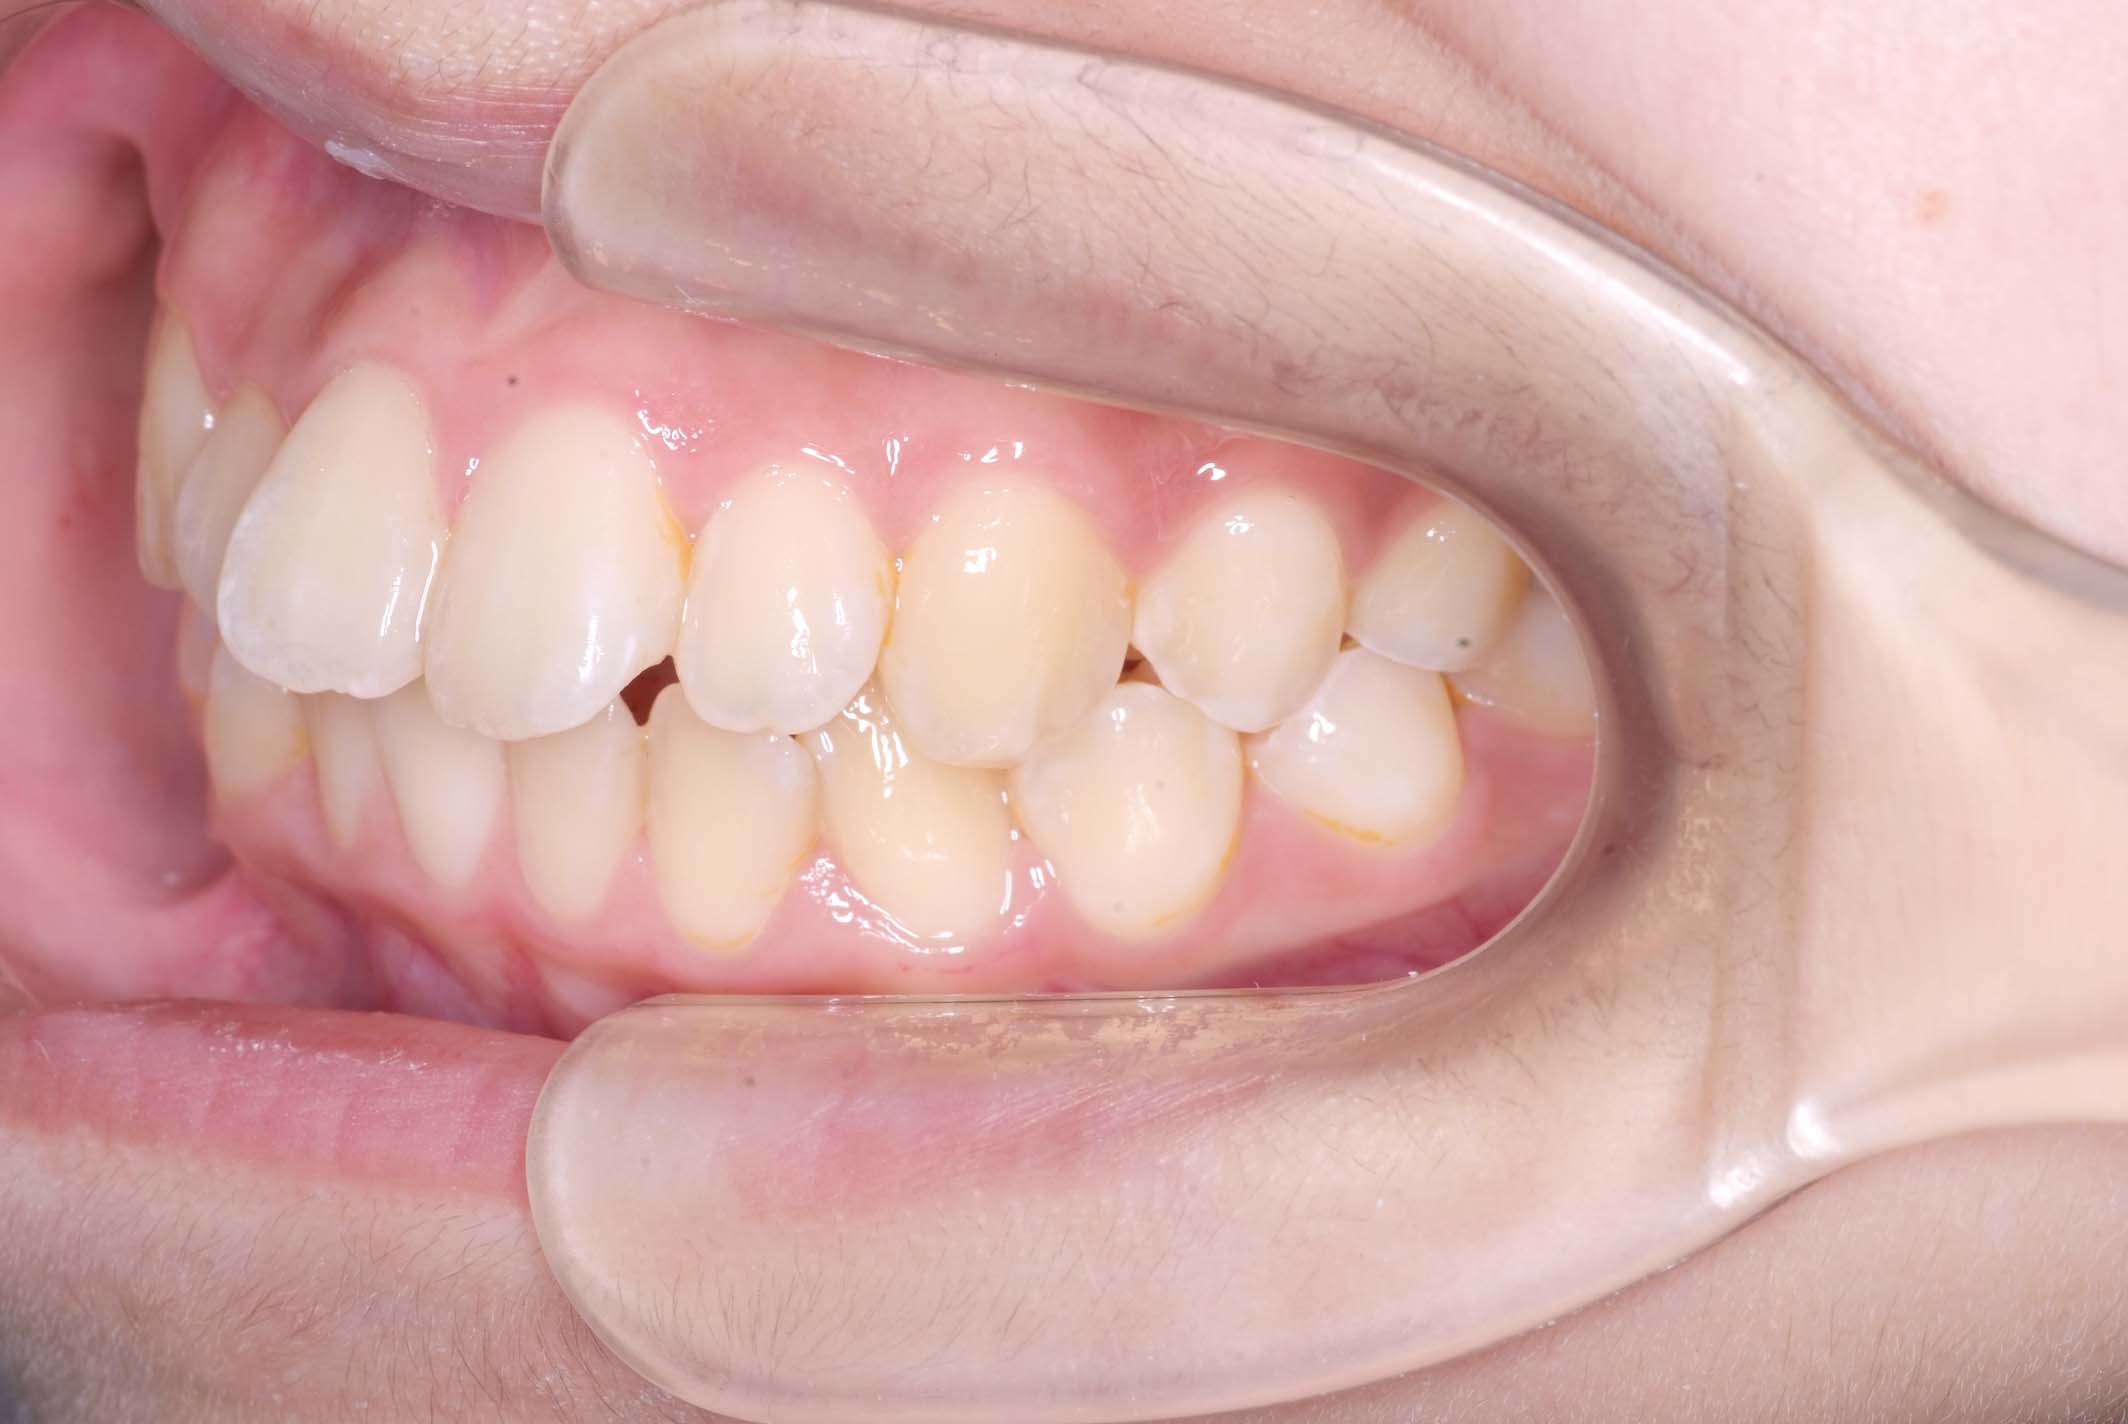

初診時年齢8才の女子で、前歯部開咬を気にして来院されました。

検査の結果、前歯部開咬と正中離開と上下顎前歯唇側傾斜を伴うアングルⅡ級1類不正咬合と診断しました。

前期治療は、リンガルアーチで正中離開を改善し、その後は歯列矯正用咬合誘導装置(マイオブレース)を使用して舌のトレーニングを行いました。後期治療は、上下左右4番を抜歯の上、セルフライゲーションブラケット装置(クリアティ・ウルトラ)で行いました。治療期間は前後期合わせて6年6ヶ月でした。通院回数:60回。